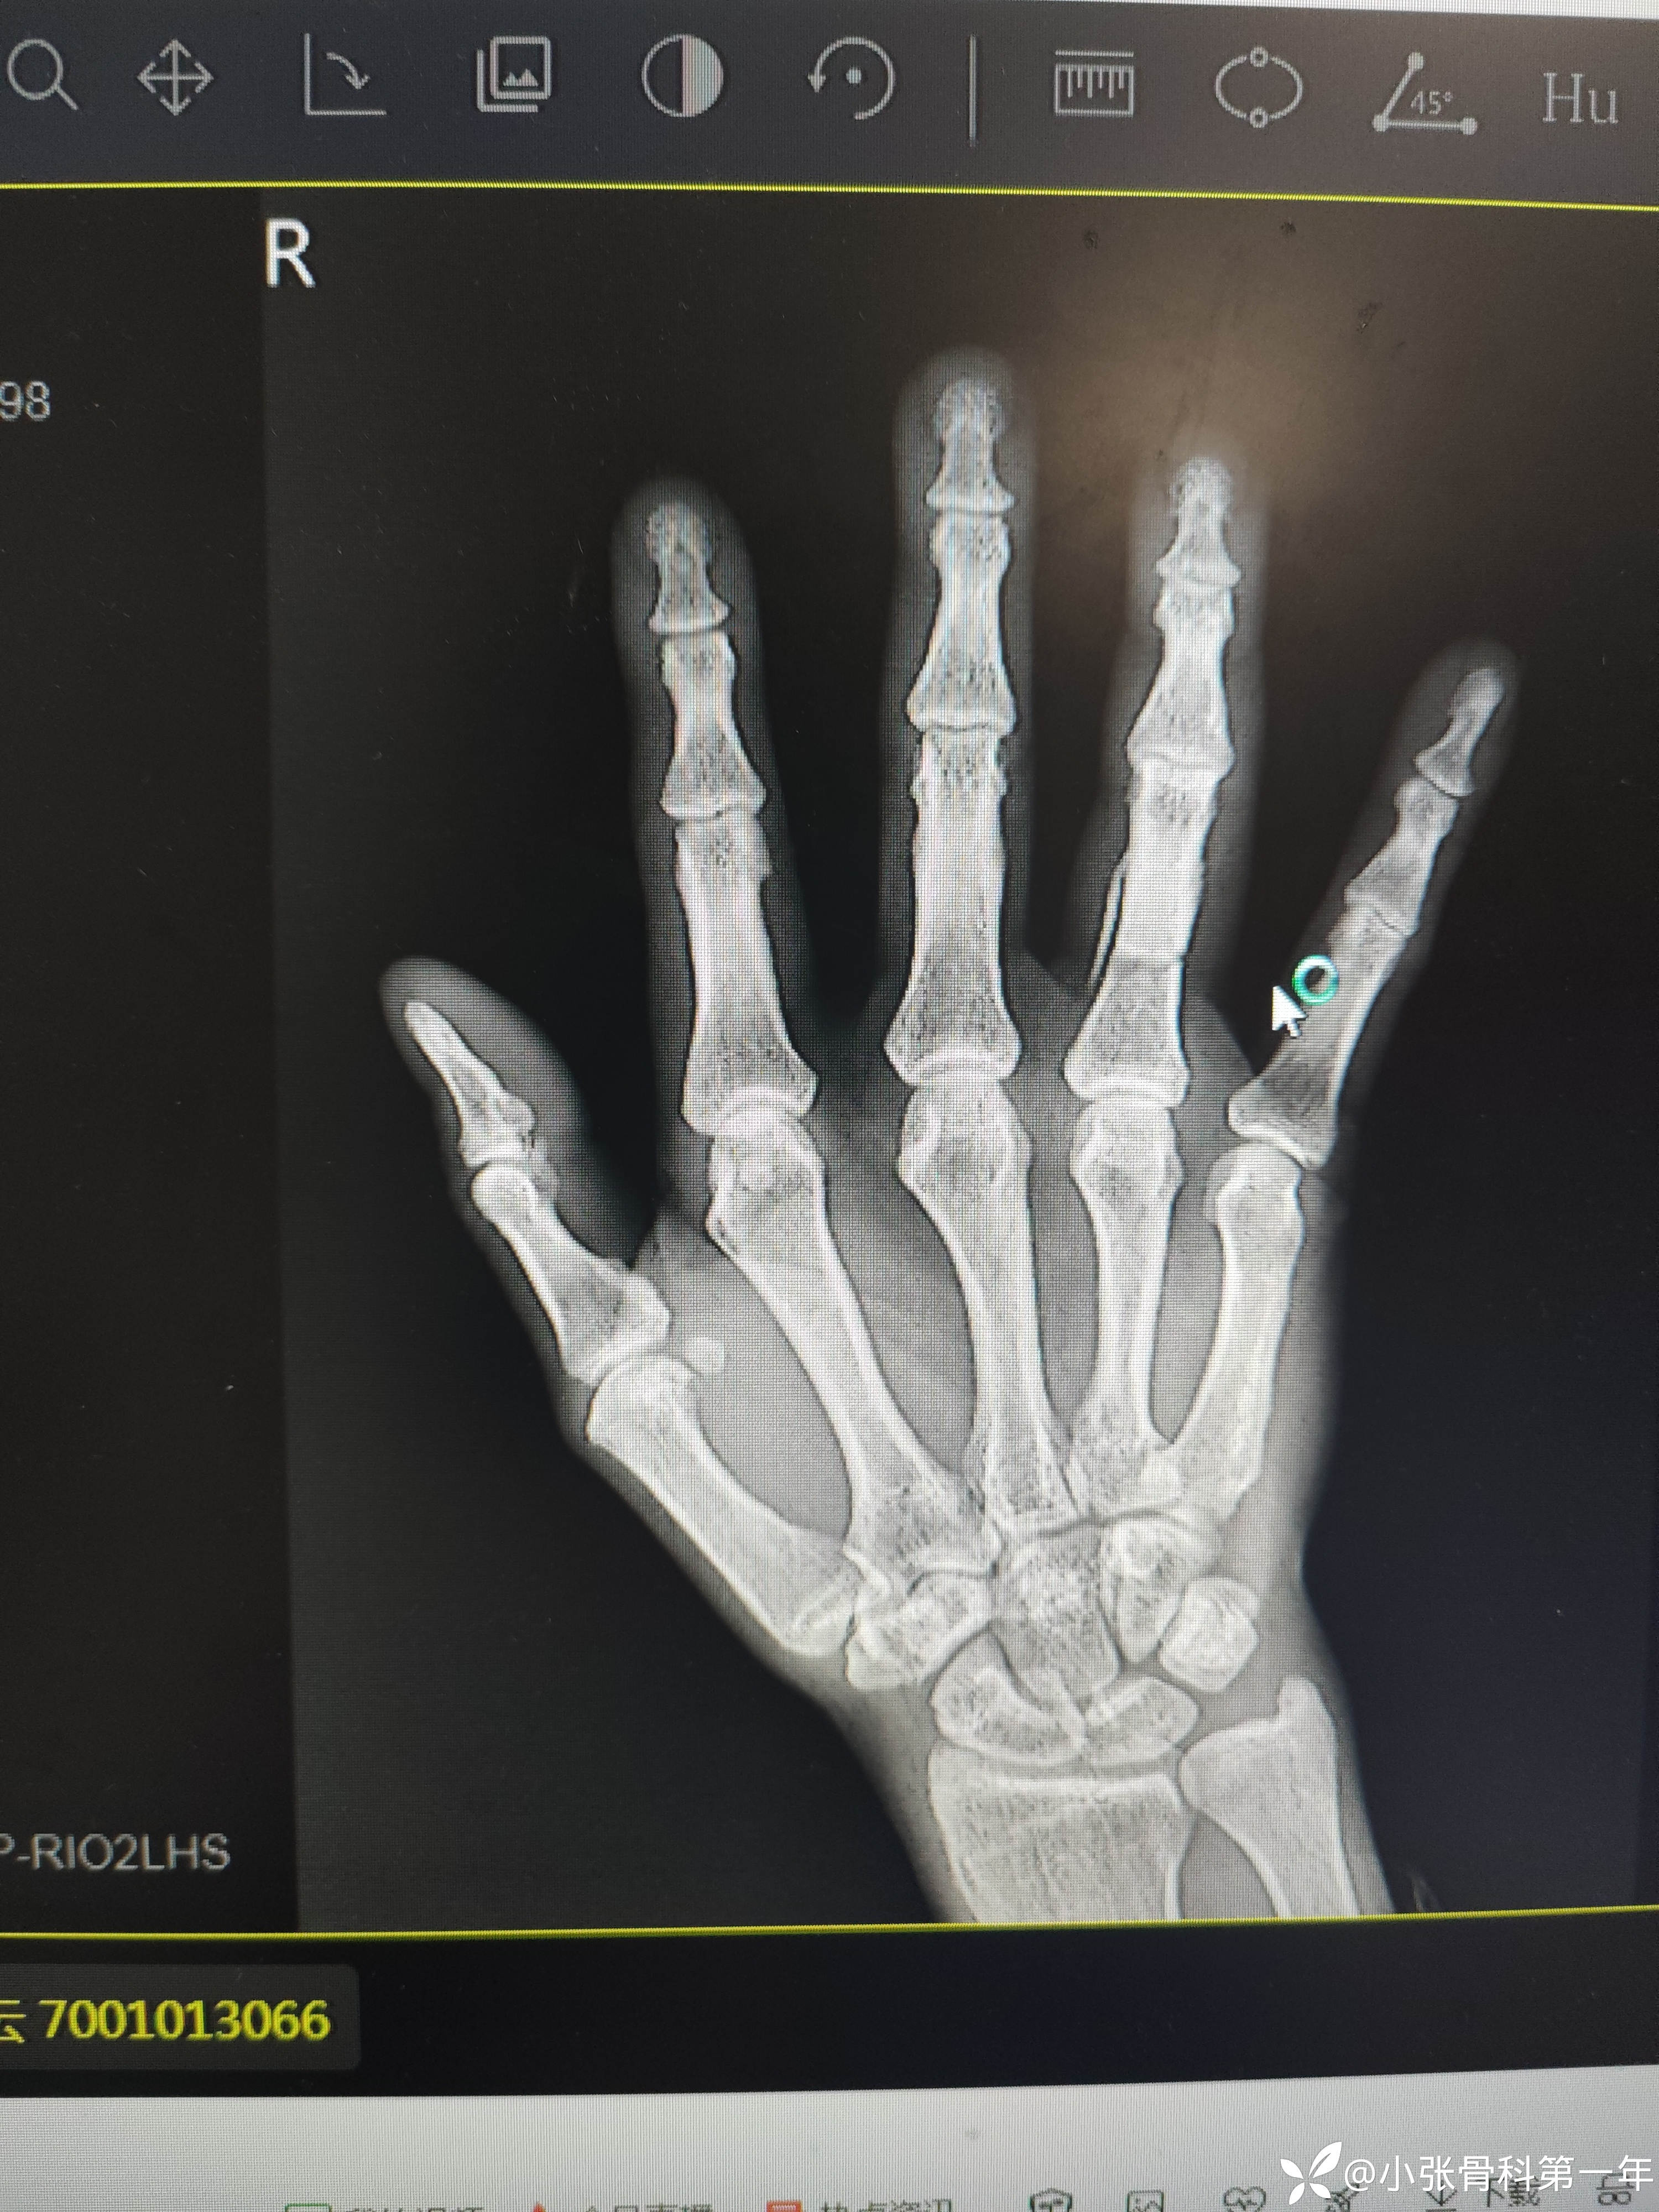

患者中老年男性,58岁,夹伤致右手环指疼痛流血伴活动受限3小时入院。

急诊闭合复位克氏针内固定术